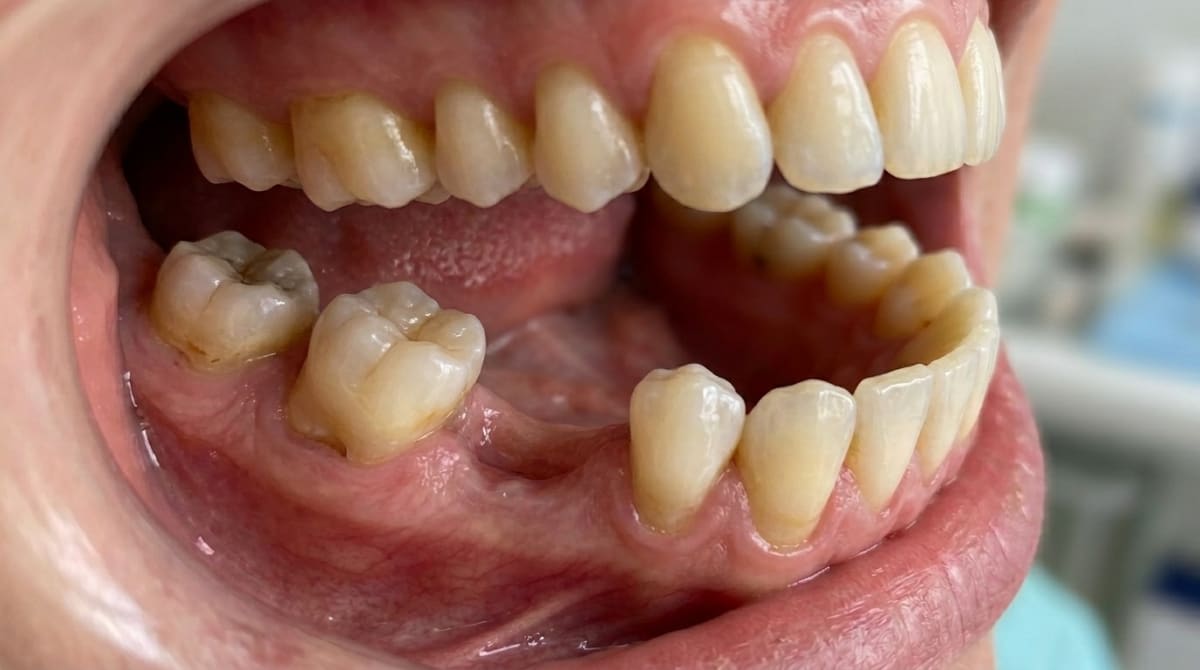

Gum disease and bone loss — As the bone supporting your teeth shrinks, the contact points between teeth weaken and small spaces open up. Periodontal bone loss is the leading cause of food trapping in adults (Tonetti et al., 2018).

Teeth drifting out of position — Chronic inflammation weakens the periodontal ligament, which holds each tooth in place. Once weakened, teeth can shift under normal chewing forces (Brunsvold, 2005).

Worn or damaged fillings — Old restorations gradually lose their original shape, creating gaps where food gets trapped. High caries-risk patients are especially prone to restoration failure (Opdam et al., 2014).

Decay between teeth — Cavities that form between teeth (interproximal decay) break down the contact point, creating a direct path for food.

Drifting typically appears as front teeth moving forward or outward, creating small triangular gaps between them. By the time these gaps are visible, significant bone loss has often already occurred (Papapanou, 1996).